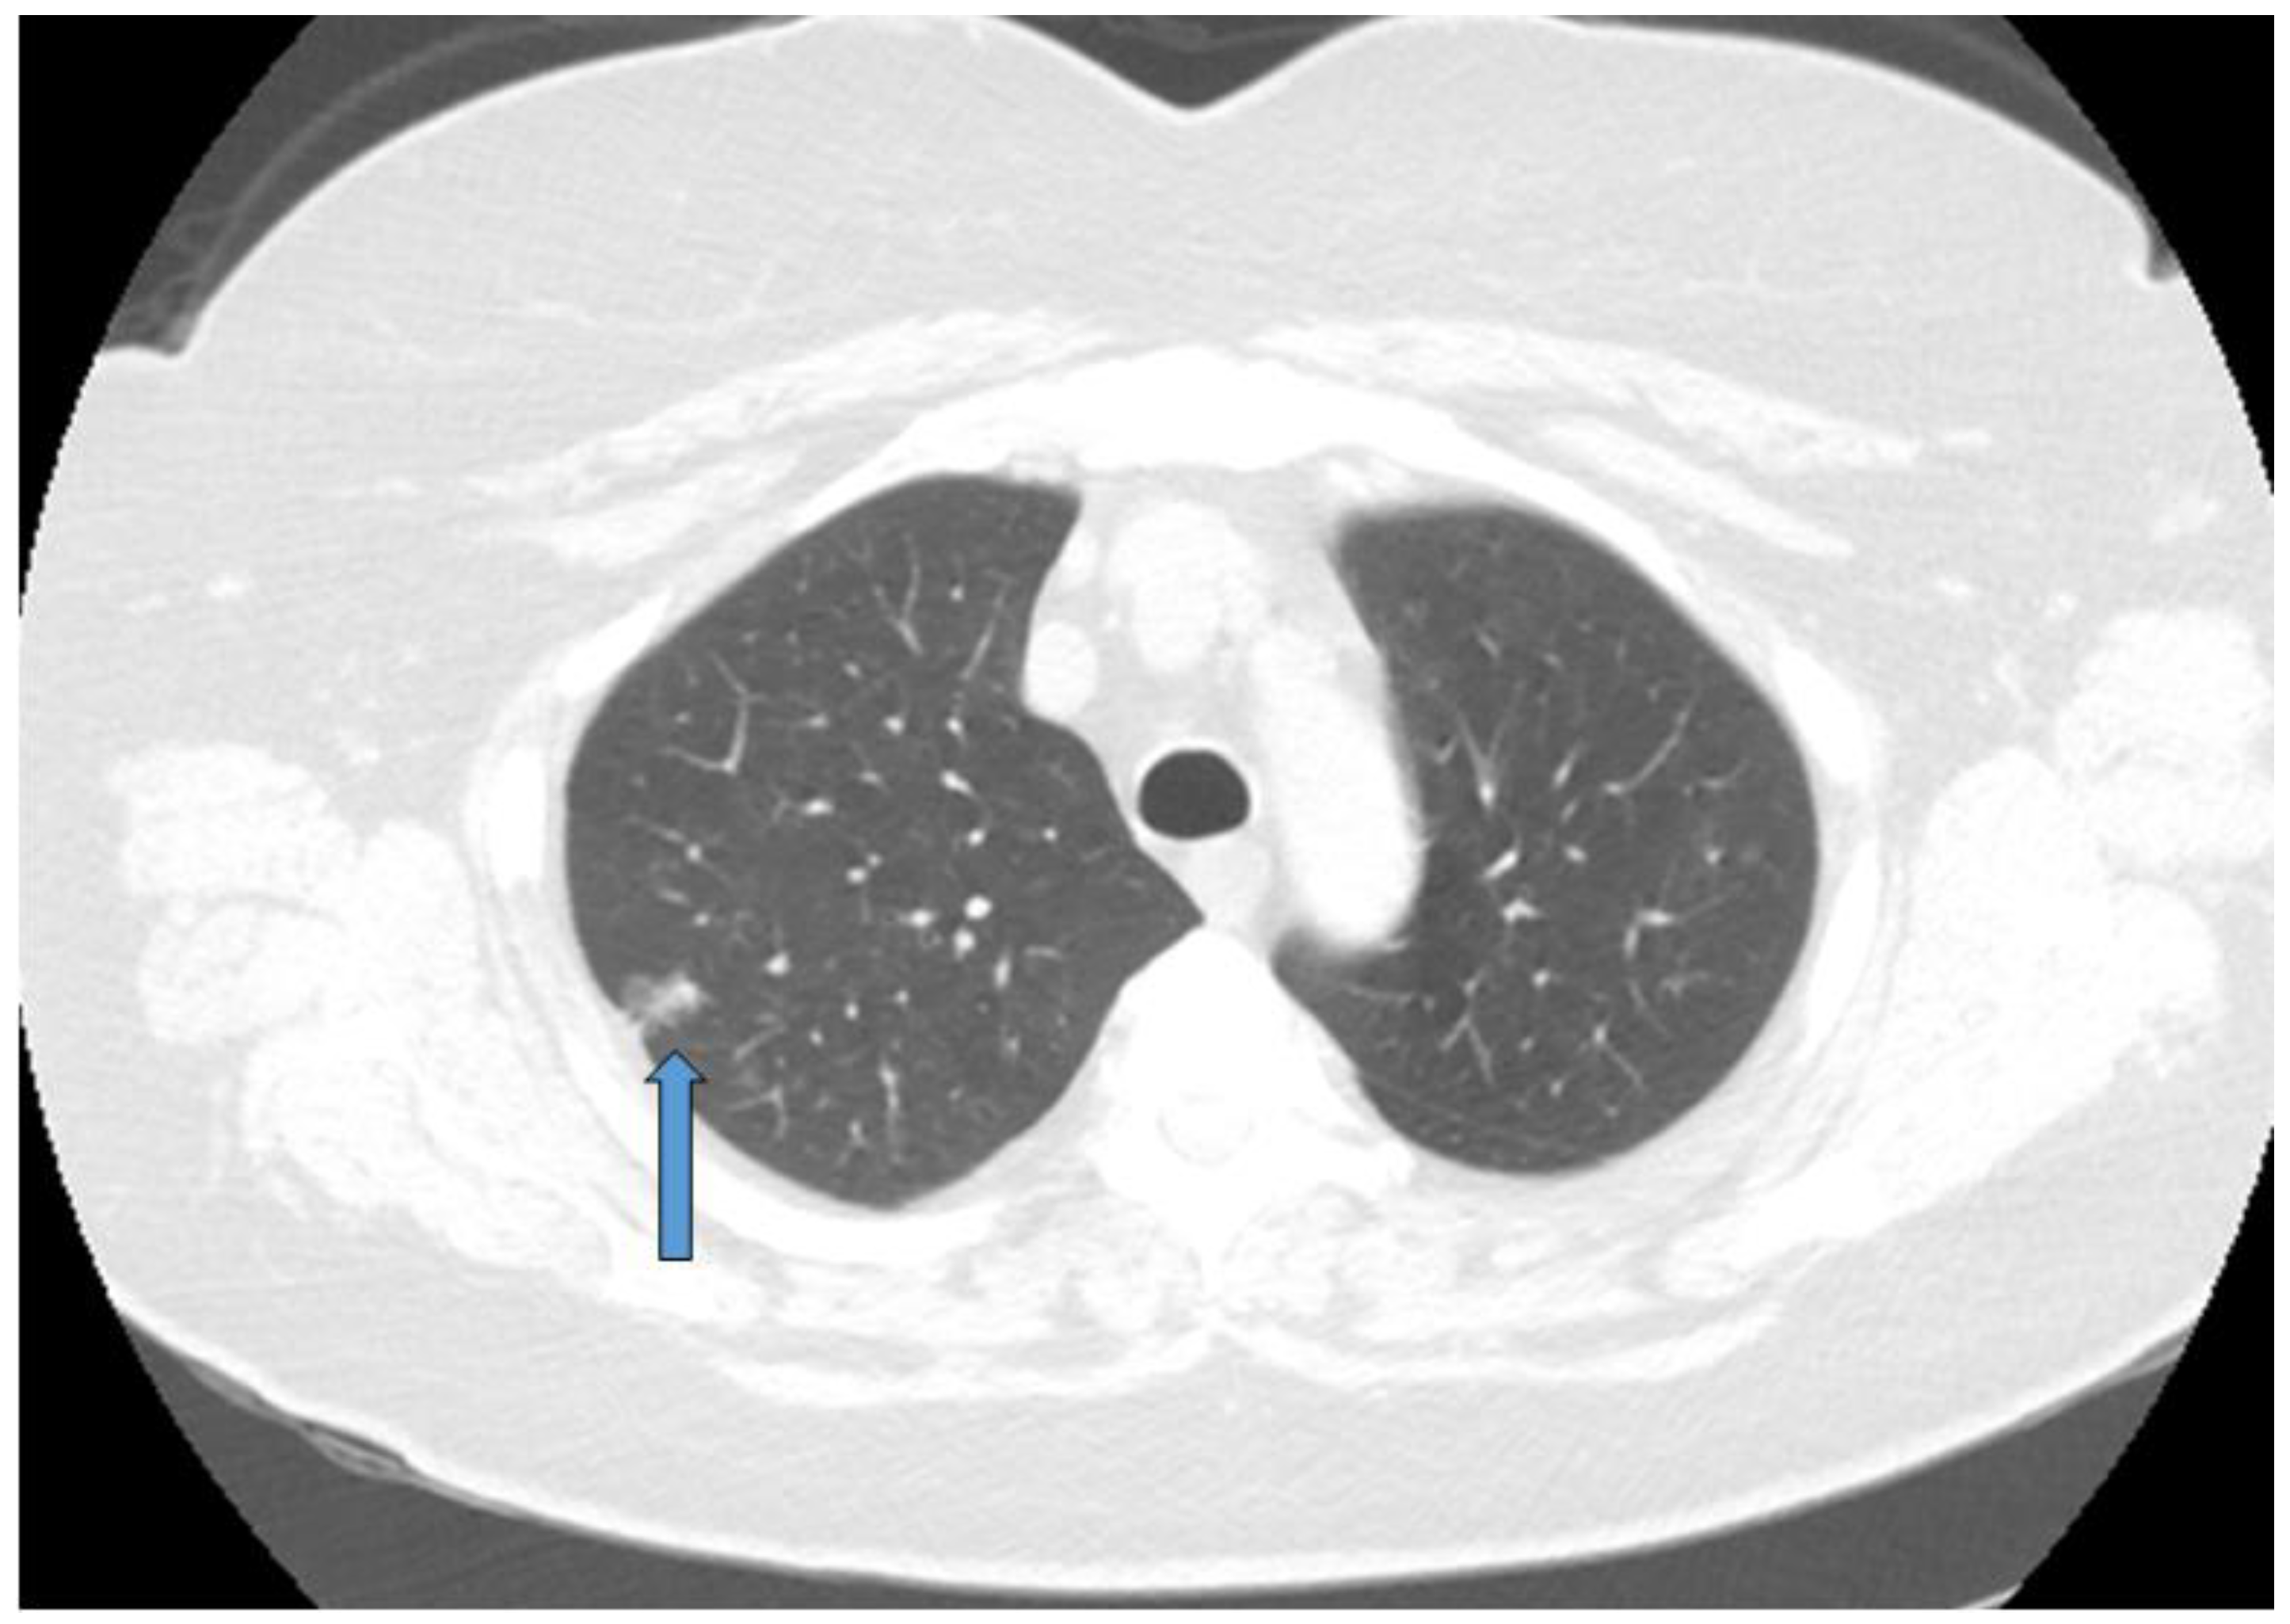

Abstract

1.4. Workup